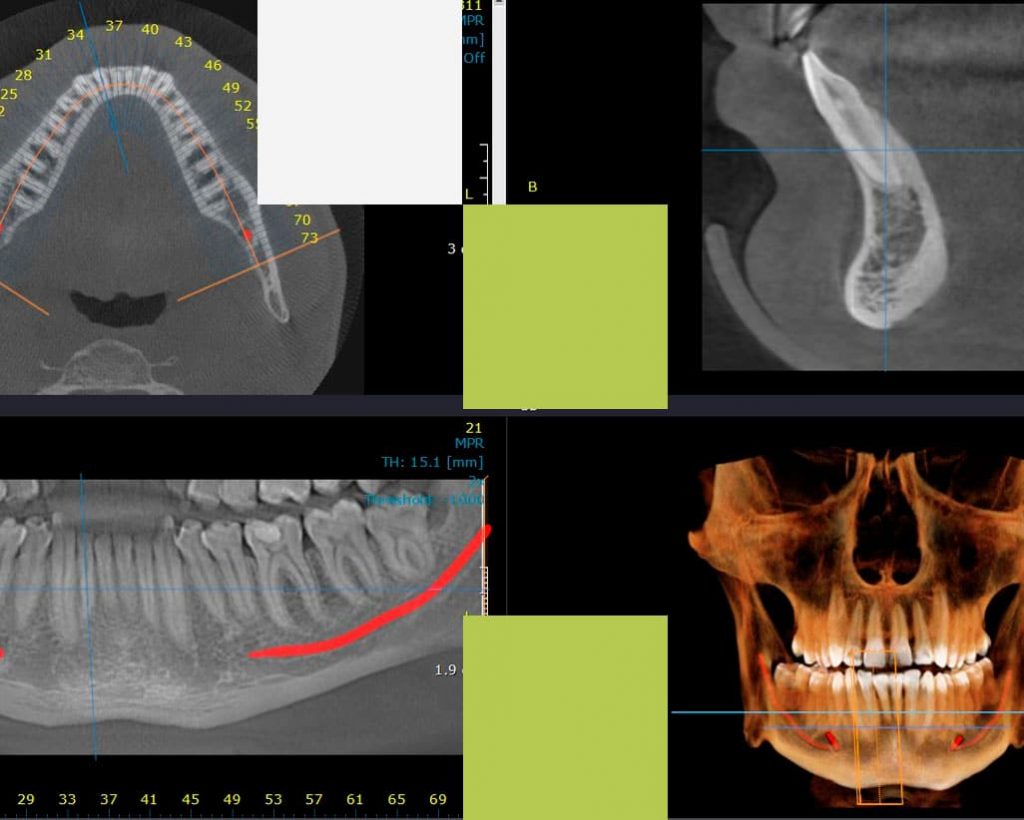

1. Radiografia digitală panoramică

Radiografia panoramică (Ortopantomografia) furnizează medicului o imagine de ansamblu a dentiției și a elementelor anatomice maxilo-faciale înconjurătoare. Această radiografie se realizează înainte de orice tratament stomatologic, astfel încât medicul să aibă o imagine completă a cazului pe care îl tratează, să evalueze posibile leziuni inflamatorii sau dinți neerupti, structura osoasă de susținere, articulațiile temporo-mandibulare, să vizualizeze molarii de minte, rapoartele dinților cu repere anatomice învecinate (nerv alveolar, sinus maxilar) sau posibile fracturi osoase maxilare sau mandibulare.